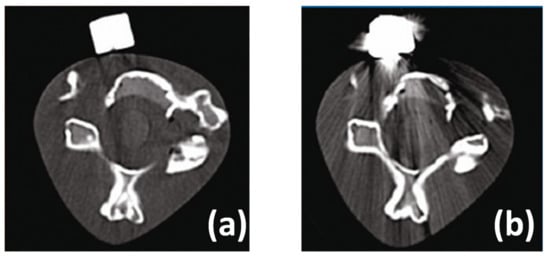

| computed tomography | CT |

- Cheruvu, B.; Venkatarayappa, I.; Goswami, T. Stress Shielding in Cemented Hip Implants Assessed from Computed Tomography. Biomed. J. Sci. Tech. Res. 2019, 18, 1–5. [Google Scholar] [CrossRef]